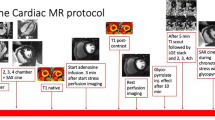

Cine magnetic resonance imaging

Cine magnetic resonance imaging (CMR) is the gold standard for the quantitative assessment of left ventricular mass and volumes, from which systolic function may be determined [86]. This non-ionising imaging method has excellent three-dimensional spatial resolution. As a consequence of the complex spatial data acquisition in either the gradient echo or the phase-contrast imaging technique, there are some limitations in temporal resolution. Most CMR technologies have a time resolution ≥ 30 ms; that for fast breath-hold gradient echo imaging and CMR fluoroscopy resolution is 15–25 ms and that for CMR tissue tagging is ≥20 ms [87]. Gradient echo imaging uses repetitive radiofrequency pulses gated to the electrocardiogram so that cine images may be generated during a single breath-hold. Phase-contrast CMR allows velocity encoding of moving structures and blood using the spin phase shift as the basic principle for velocity measurement. Commercially available quantitative CMR software uses spatial modulation of magnetisation (SPAMM) tagging to characterise regional wall motion inhomogeneities [88]. This technique may offer greater accuracy for the detection of regional systolic dysfunction analogous to speckle tracking-derived strain and strain rate. However, it shares with speckle tracking the disadvantages of lower frame rates (50 frames/s) compared with pulsed tissue Doppler imaging, which is not ideal for the assessment of diastolic function. At present, the use of CMR for the assessment of diastolic function may be considered a research tool because of its high cost, limited availability and the need for time-consuming offline data reduction and analysis associated with non-ideal temporal resolution.

The use of contrast agents such as gadolinium to mark scarred myocardium, fibrosis or inflammation by delayed contrast enhancement has been integrated into clinical routine. Magnetic resonance spectroscopy has the potential to recognise changes in myocardial bioenergetics and metabolism, such as increased lipid supply by 1H-magnetic resonance spectroscopy and altered high-energy phosphate metabolism assessed by 31P-magnetic resonance spectroscopy for measuring the phosphocreatine–ATP ratio (PCr/ATP). These technologies may open new windows on the links between altered metabolism and function in the diabetic heart. First reports demonstrate reduced diastolic function in well controlled patients with uncomplicated type 2 and type 1 diabetes compared with age-matched controls associated with impaired myocardial energy metabolism [38, 49]. Reduced diastolic function has also been observed in type 2 diabetic patients with myocardial steatosis [44] and in middle-aged compared with younger healthy individuals, but is improved in middle-aged individuals on long-lasting aerobic training, paralleled by the PCr/ATP ratio [89].

Summary of imaging techniques

Apart from histological and molecular changes in the diabetic myocardium, which are not the focus of this review, there is growing evidence that diastolic and systolic myocardial dysfunction can be and should be routinely quantified by tissue Doppler imaging. Low cost, wide availability, superior temporal resolution and on-line velocity analysis make pulsed tissue Doppler the imaging modality of choice to investigate the presence of left ventricular dysfunction in diabetes or the metabolic syndrome. A specific research advantage of CMR techniques is the ability to assess changes in tissue composition as well as alterations in myocardial metabolism by spectroscopy.